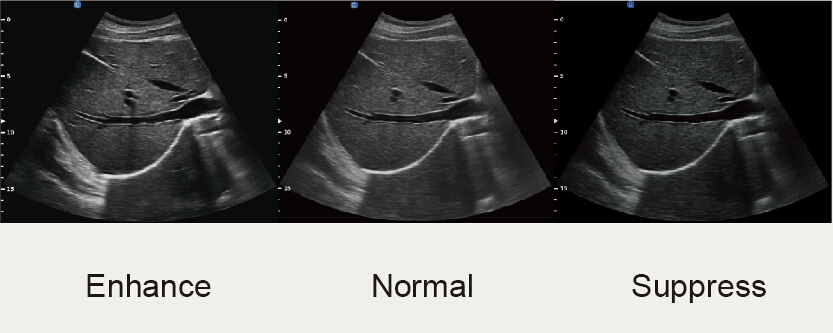

X-contrast

● La resolución de contraste se puede establecer en 3 niveles diferentes según las diferencias de los tejidos.

● Activado por una de las claves: Aumentada, Normal, Reducida.